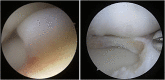

Purpose of review: Discoid lateral meniscus (DLM) is a well-known meniscus variant, and comprises excess and thickened meniscal tissue, altered collagen ultrastructure, and peripheral instability. This article presents a comprehensive review on current knowledge of DLM, focusing on pathology in parallel with surgical techniques and outcomes.

Recent findings: A paradigm shift in surgical management of DLM is taking place as knee surgeons are seeing more patients with long-term sequelae of partial lateral meniscectomy, the standard treatment for DLM for many years. Surgical treatment has evolved alongside the understanding of DLM pathology. A new classification system has been proposed and optimal surgical techniques described in recent years. This article highlights up-to-date evidence and techniques in management of both acute DLM tears and joint restoration following subtotal meniscectomy for DLM. Surgical management of DLM must be tailored to individual pathology, which is variable within the diagnosis of DLM. We present an algorithm for management of DLM and discuss future directions for the understanding and treatment of this debilitating condition.